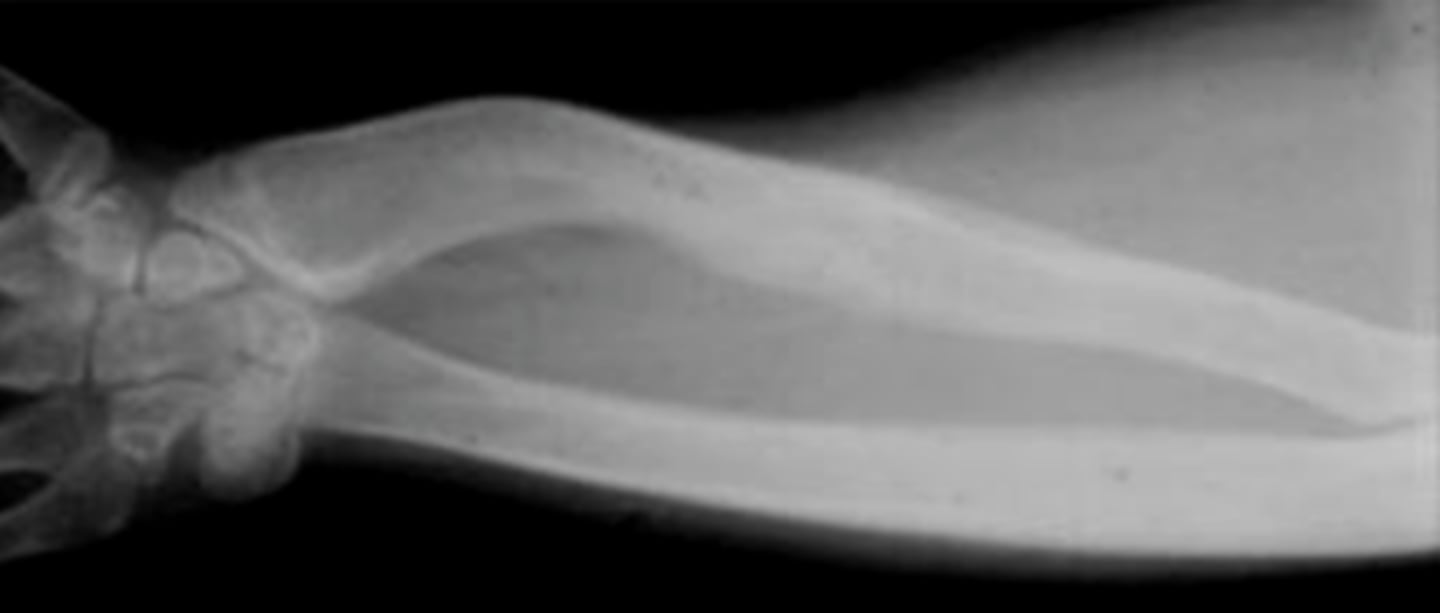

Madelung deformity

Shortened distal radius with abnormal ulnar tilt of its distal articular surface. Think of Leri Weill Dyschondrogenesis

Leri Weill Dyschondrogenesis

pseudoautosomal at SHOX (X chromosome, pseudoautosomal region). Mesomelia (resultant short stature). Most people with the condition also have an abnormality of the wrist and forearm bones called Madelung deformity, which may cause pain and limit wrist movement.